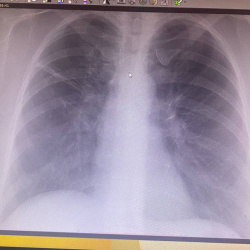

Человек 45 лет. ничего не беспокоит. Профилактически сделан снимок. Какая патология каково ваше мнение?